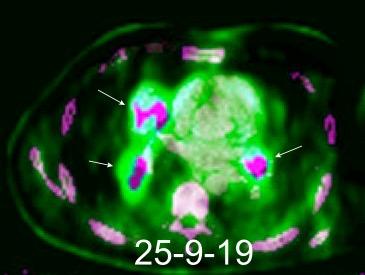

NÓDULOS MÚLTIPLES CON CALCIO/HUESO

Tuberculomas que crecen TUBERCULOMAS

Metástasis

Infección granulomatosa

Embolismo séptico

Enf. de Wegener

Sarcoidosis

Linfoma

Nódulos reumatoideos

Neumonía por varicella

Goo JM, et al. Pulmonary tuberculoma evaluated by means of FDG PET: findings in 10 cases. Radiology. 2000./Chang JM et al.

False Positive and False NegativecFDG-PET Scans in Various Thoracic Disease Korean J Radiol 2006./ Pipavath S. Multiple welldefined nódulos en Stern-Gurney. EXPERTddx. Chest. Amirsys.2011